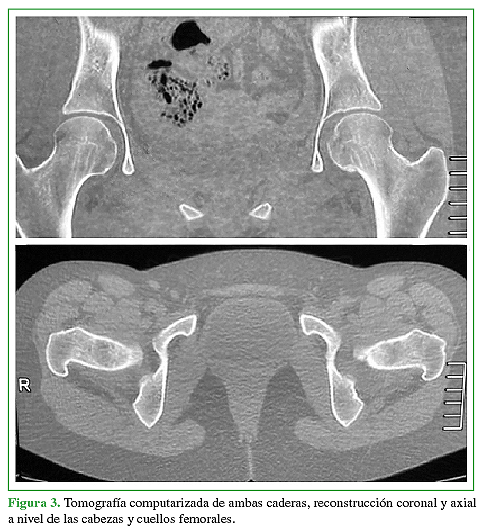

Se presenta un caso de un paciente femenino de 22 años con dolor en cadera izquierda de larga evolución sin antecedentes reelevantes.Descargas